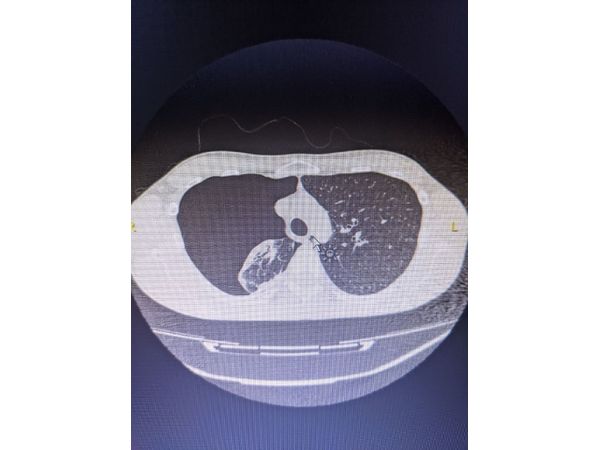

КТ органов грудной клетки от 28 января выявила правосторонний субтотальный пневмоторакс. Тогда бригада скорой медицинской помощи доставила мужчину в отделение торакальной хирургии.

Рентгенография органов грудной клетки при поступлении 28 января выявила правосторонний пневмоторакс, лёгкое при этом уменьшилось, спало и не участвовало в дыхании. В правом лёгком также обнаружили скопление воздуха (подкожную эмфизему).

Буллёзная эмфизема лёгких. Правосторонний спонтанный пневмоторакс.

Под общей анестезией в точке ранее стоявшего дренажа сделали прокол и через торакопорт ввели оптическую систему, которая позволила осмотреть правое лёгкое: междолевые борозды не заращены, в нижних отделах скопилось около 40 мл прозрачно жёлтой серозной жидкости без запаха. После её выведения удалось лучше рассмотреть лёгкое: оно было розовым и воздушным, сосудистый рисунок внутренней плевры верхней доли усилен, в верхнем сегменте находился воздушный мешок размером до 0,5 см, рёберная плевра не изменилась, но сосуды расширились и воспалились.